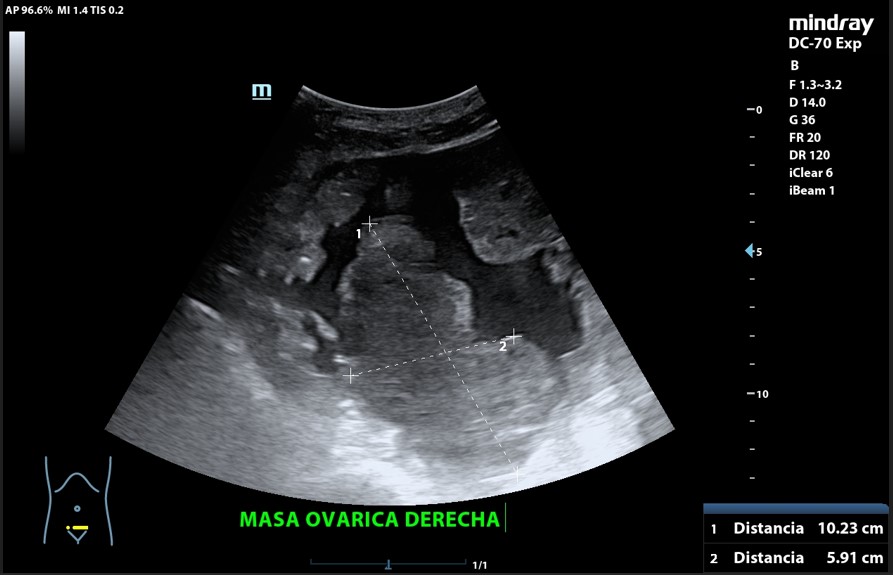

Presencia de 2 masas pélvicas bien delimitadas heterogéneas que captan Doppler, una de 5 cm de diámetro y otra ovalada de 10 cm de longitud. Líquido ascítico peritoneal, que también se observa alrededor del bazo y en espacio de Morrison. Derrame pleural derecho.

Tumoración ovárica bilateral.